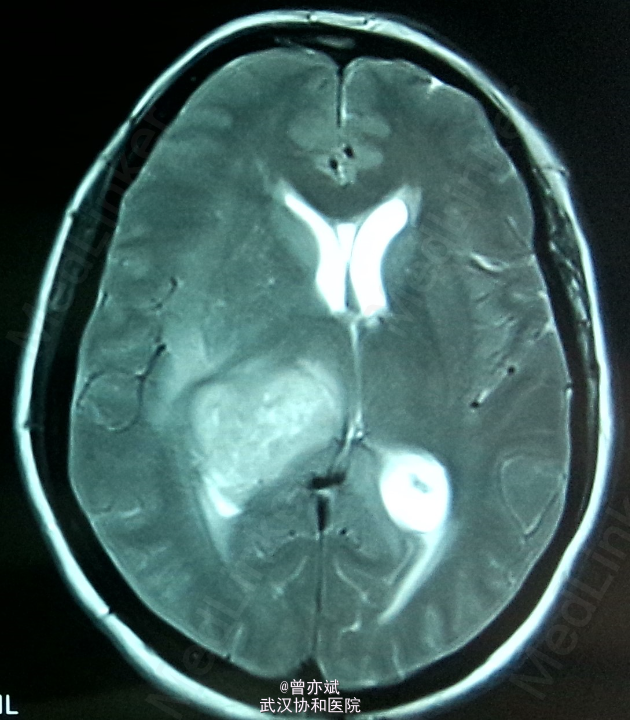

侧脑室占位一例

主诉:间歇性头痛半年余,加重一月 简要现病史:患者半年前无明显诱因出现间歇性头痛,无发热、恶心呕吐、肢体无力、抽搐等症状,近一月来,头痛症状加重,当地医院行MRI提示侧脑室占位。

专科查体神志清楚,双侧瞳孔等大等圆,直径约3mm,光反射灵敏,四肢肌力4级,生理反射村子啊,病理反射未引出。 MRI提示右侧 脑室巨大占位

诊断:右侧侧脑室占位:室管膜瘤? 处理:手术治疗